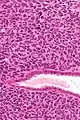

Micrograph of a uterine adenosarcoma showing a mitotically active malignant stroma and benign glands. H&E stain.

Uterine adenosarcoma have, by definition, a malignant stroma and benign glandular elements. The World Health Organization (WHO) criteria have a mitotic rate cut point; however, this is often disregarded, as bland-appearing tumours with a low mitotic rate are known to metastasize occasionally.[2]